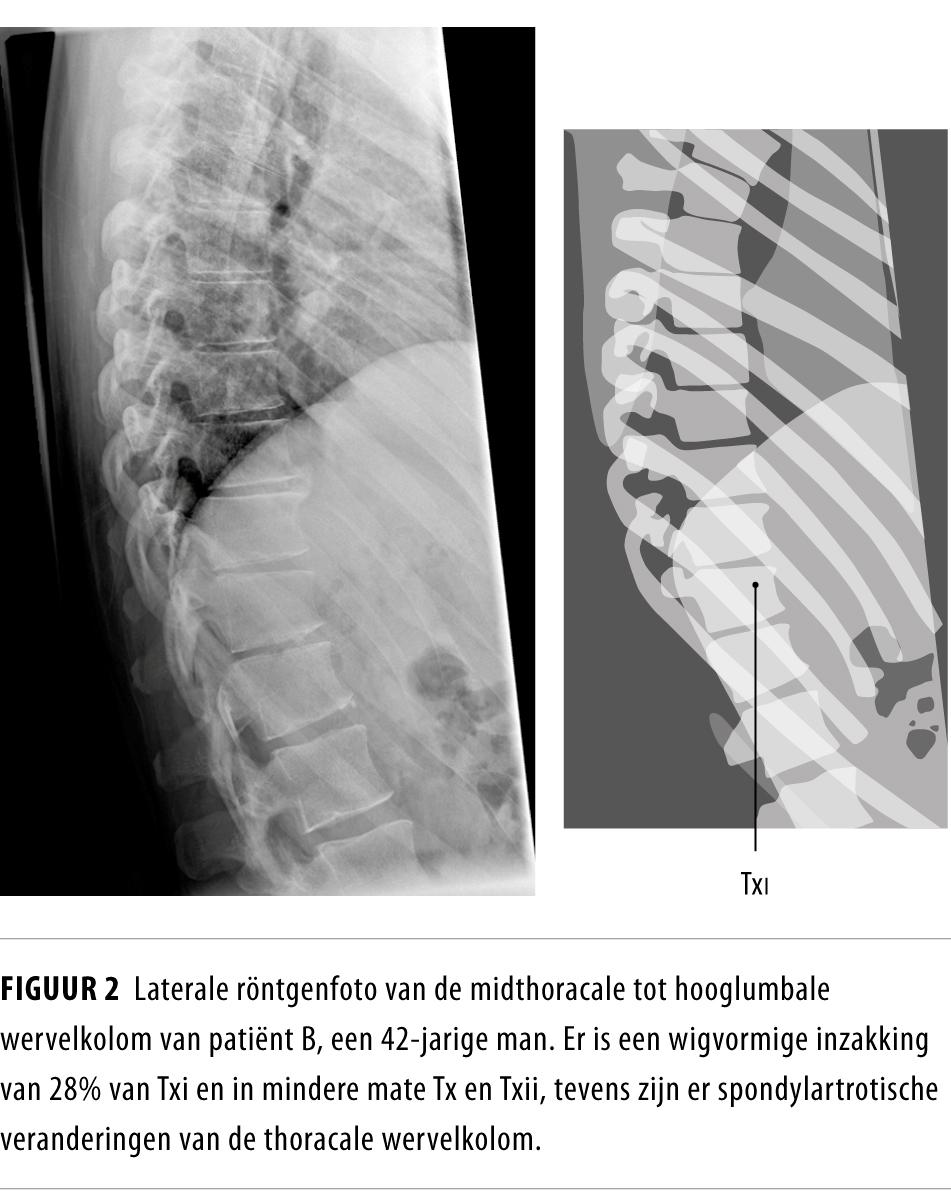

Osteoporotische wervelfracturen of ziekte van Scheuermann? NTvG